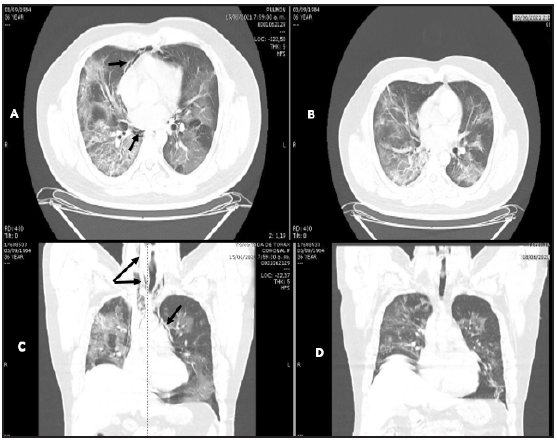

Figure 1 Patient 1. A and C: Simple chest CT. Axial and coronal planes. Air surrounding the vascular structures (black arrows) with bilateral ground glass, cobblestone, consolidated alveolar infiltrate areas extending to the neck. B and D: air reabsorption four days later.